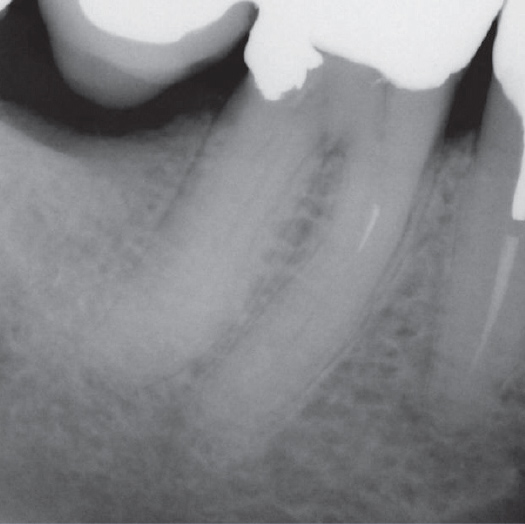

Before

Before Root Canal treatment